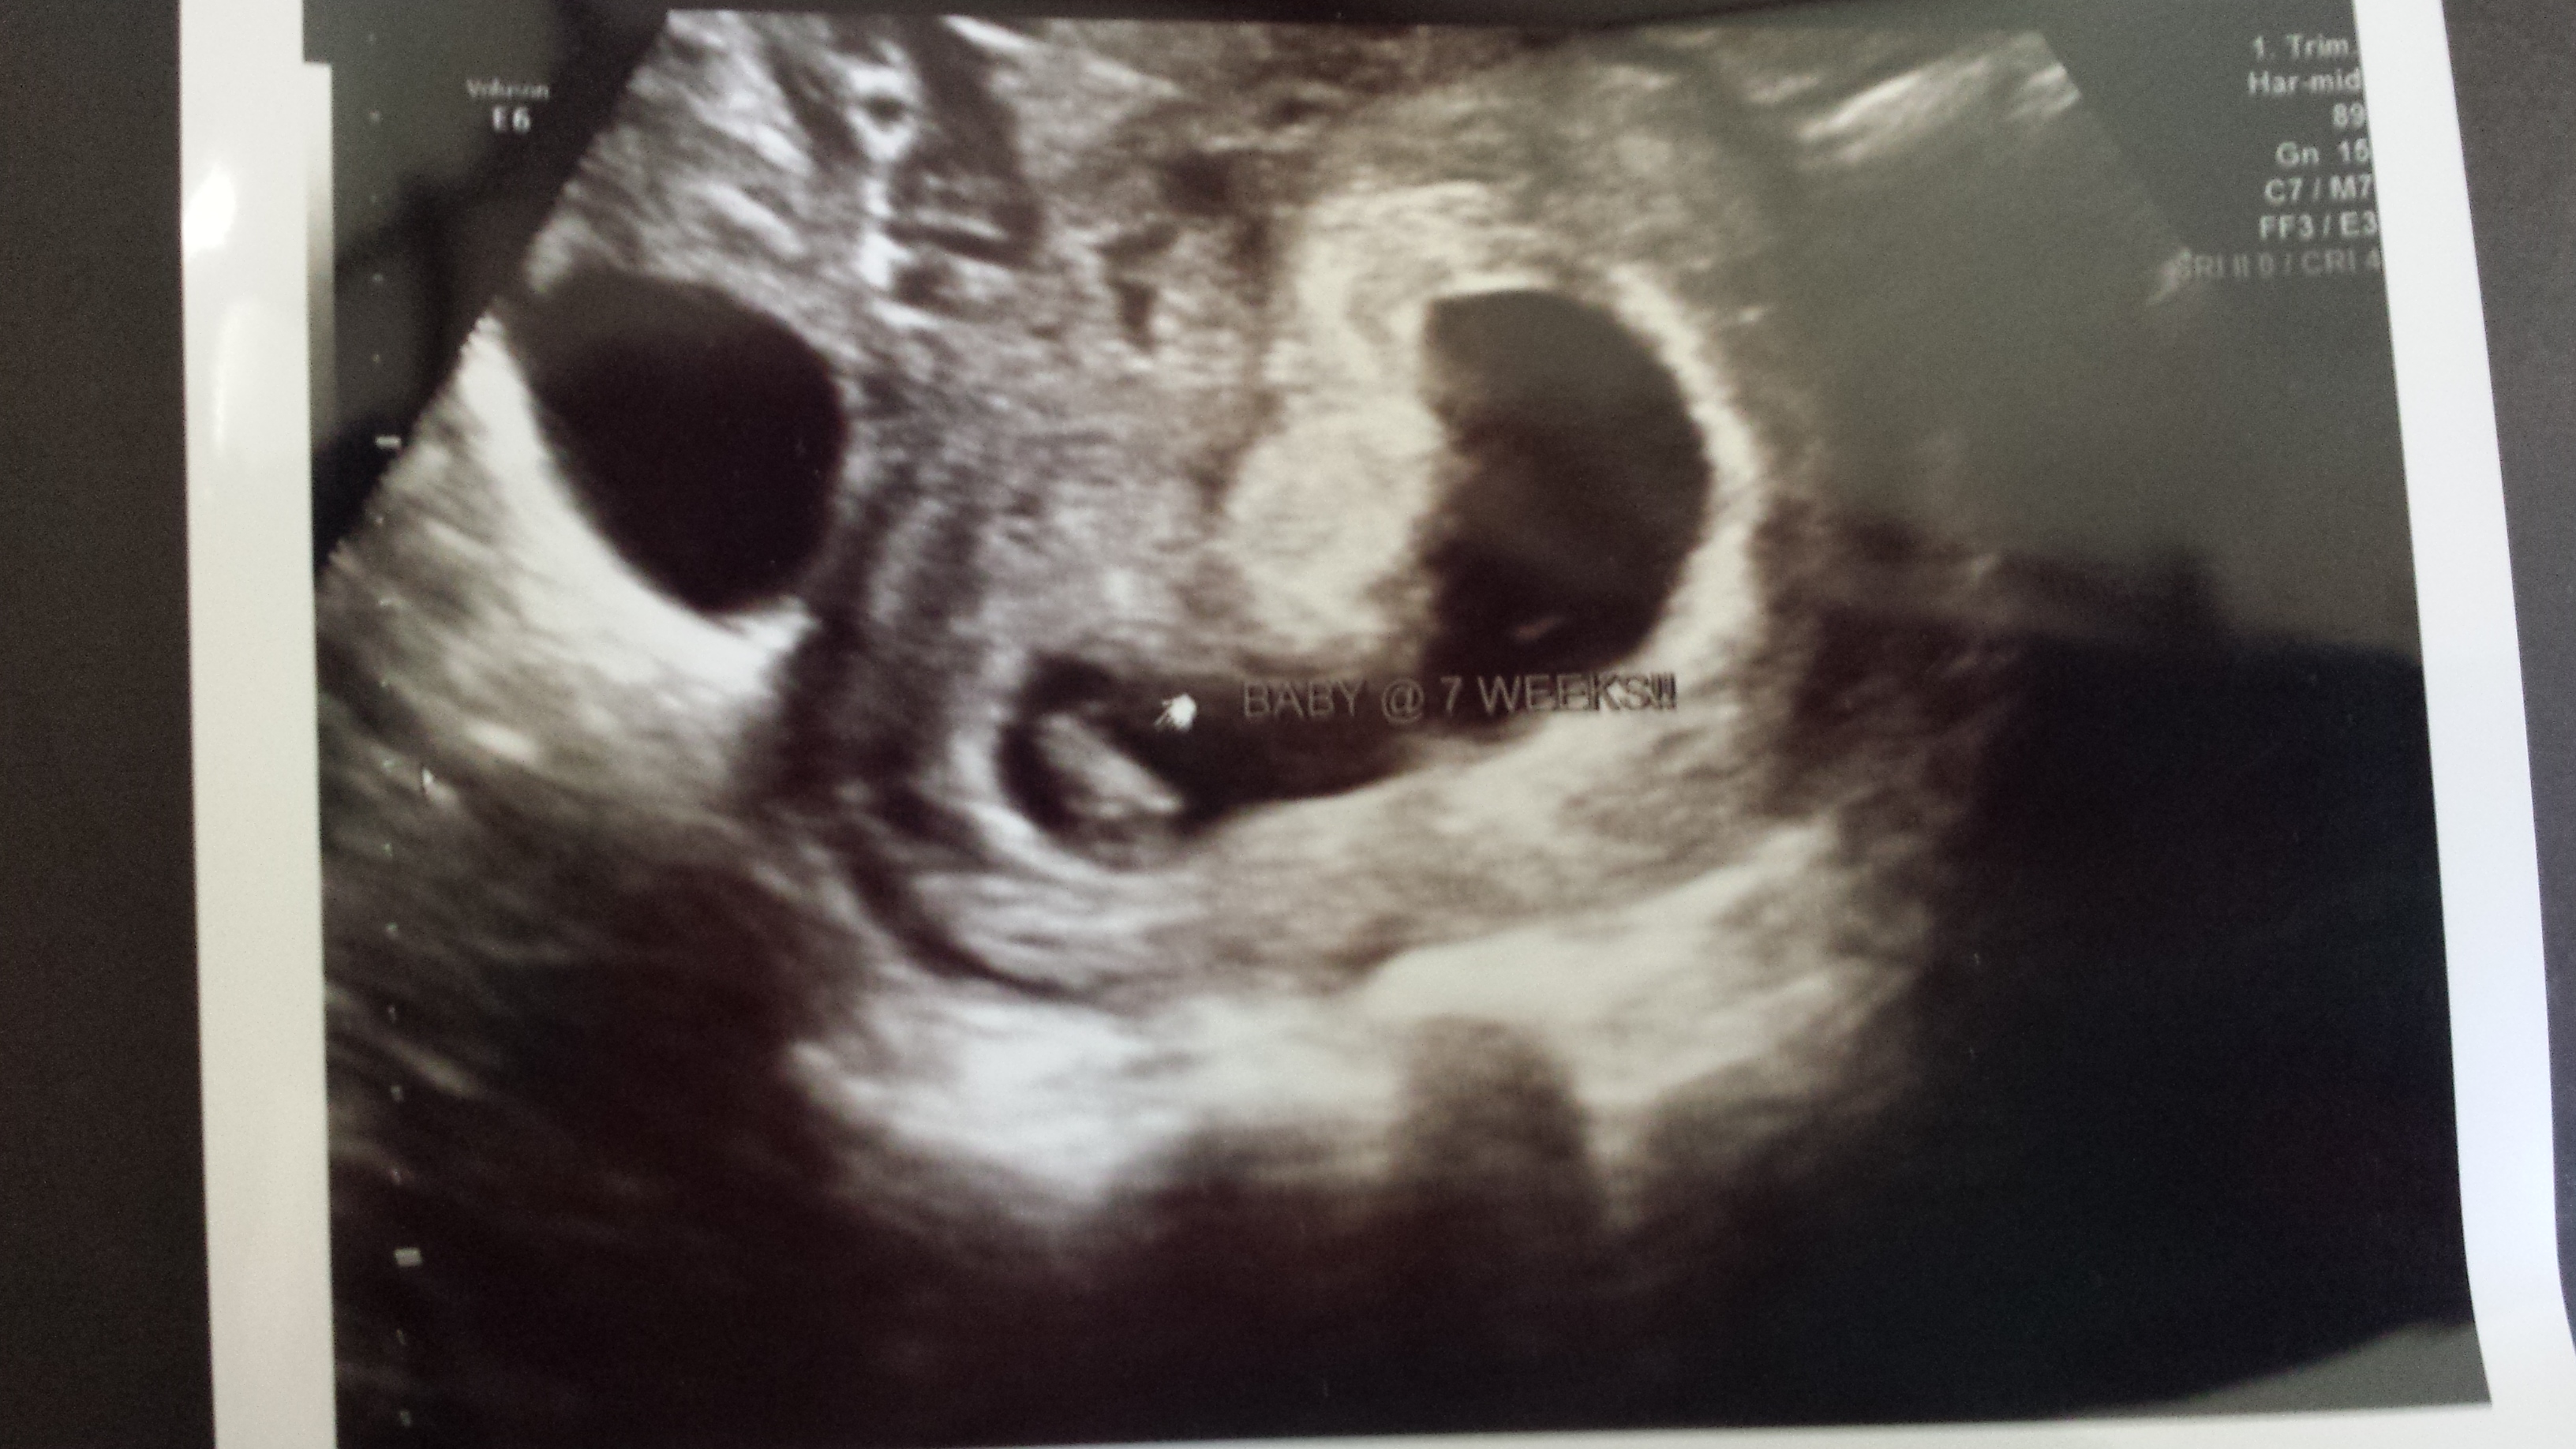

I have never posted on this site but been a member for a while. I had a quick ? if you ladies dont mind. I had an U/S done at 9w4d. I am now 16w5d but its so bugging me and wanted to know if any of you ladies had one that looked similar? This is my 3rd pregnancy so this is new for me. Its a view of babies head and just wondering what the 'extra' black hole to the right is? I know I haven't ever posted, but would appreciate any feedback. Thank you ![]()

I've had 2 ultrasounds since then (NT scan & AS), everything is perfect.